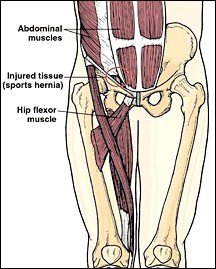

A sports hernia is a tear in the muscles of the lower abdomen. It causes pain in the lower abdomen or groin. Men get it more than women. The pain from a sports hernia usually begins gradually. Over time, athletic activity involving lifting, twisting and straining can cause microscopic tears in the muscle and fascia. The runner who sprints frequently is more likely to get it than the distance runner.

Symptoms are varied but usually involve lower abdominal pain, groin pain or pain just on one side of the lower abdomen; the pain usually is worse with coughing or sneezing. To diagnose it, I will take a history and do a physical exam. The patient will have tenderness in the lower abdomen and at the top of the groin. Some tests might be done to rule out other conditions that cause groin pain. I will rule out inguinal and other types of hernias. The initial treatment for a sports hernia involves rest, chiropractic physiotherapy, a special support belt, and special exercises. With proper treatment and the best scenario, it will take a few weeks for symptoms to go away. Without treatment, it may take two to six months or much longer.

At home, an ice pack is used on the area for 20 to 30 minutes, three to four times a day to minimize the discomfort. In rare instances, if rest, chiropractic physiotherapy, etc., do not relieve symptoms, surgery should be performed. During surgery, the lower abdominal muscles and connective tissue are released and reattached and some hip muscles are loosened.